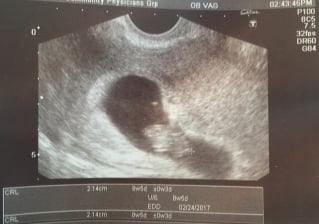

@MrsNap_515 -- this happened to me too! I'm a week ahead of you so this is the picture we got when we went back to hear the heartbeats yesterday at 6w4d. I reeeeeally wish someone had been recording our faces when the doctor told us. Exciting and terrifying! (Posting from my phone...apologies if this is huge.)

This was my ultrasound from last week at 5wks - twins - one much smaller than the other, no heartbeats yet. Hopefully I'll have a some progress on Friday given the rollercoaster of a week that it has been (for those of you following my post "50/50 chance I'm out *TW*" - you know what I mean)! FX!